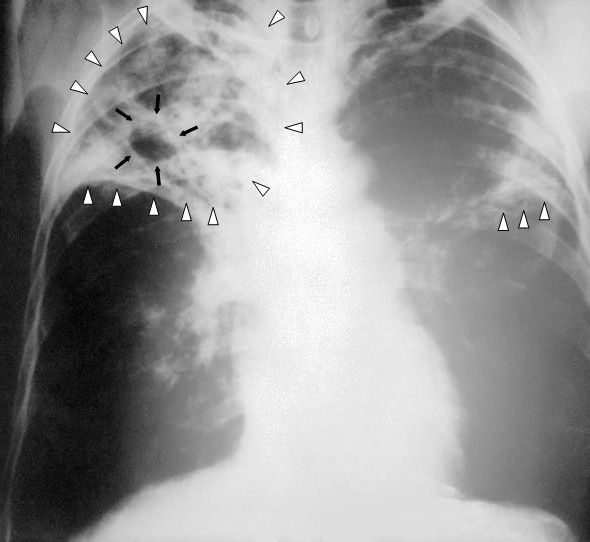

La République Démocratique du Congo (RDC) fait face à des défis persistants dans la lutte contre la tuberculose, mais des progrès significatifs ont été réalisés. Malgré une baisse mondiale de l’incidence de la maladie, le nombre de personnes atteintes de la tuberculose en RDC reste alarmant. En 2021 seulement, plus de 216 000 personnes ont été diagnostiquées, soulignant l’urgence de renforcer les efforts de prévention et de traitement. La tuberculose touche de manière disproportionnée les populations les plus vulnérables, aggravant les inégalités sociales et économiques.

Un investissement adéquat dans la santé est crucial pour combattre la tuberculose en RDC. Des ressources financières et des outils appropriés sont nécessaires pour améliorer les soins de santé, renforcer les systèmes de prévention, de diagnostic et de traitement, et combler les lacunes existantes. En allouant davantage de fonds à la lutte contre la tuberculose, le pays peut espérer améliorer le bien-être de sa population et favoriser une croissance économique durable. Il est essentiel d’investir dans la santé en tant qu’investissement pour l’avenir de la nation.